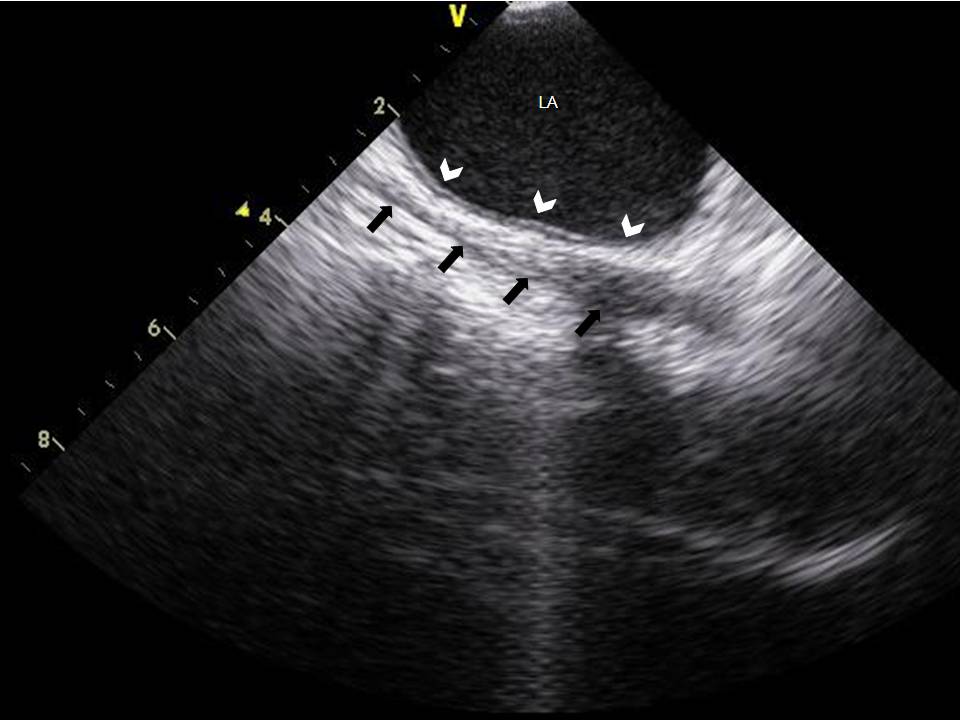

Use of ICE to Eliminate Radiation During AF Ablation

2015-07-24 13:06